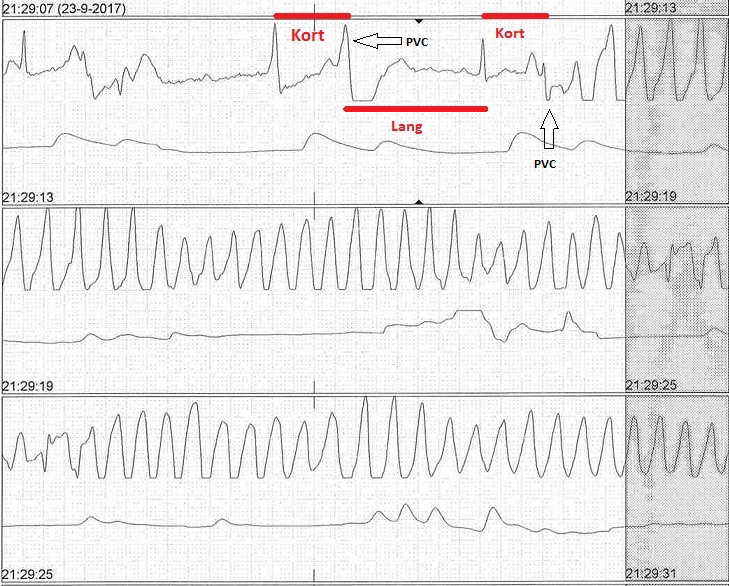

Figuur 2a: torsade de pointes; let op de volgende kenmerken:

- Verandering in amplitude en morfologie van de QRS complexen

- Kort-lang-kort patroon

- Frequentie tussen de 160 en 240/min